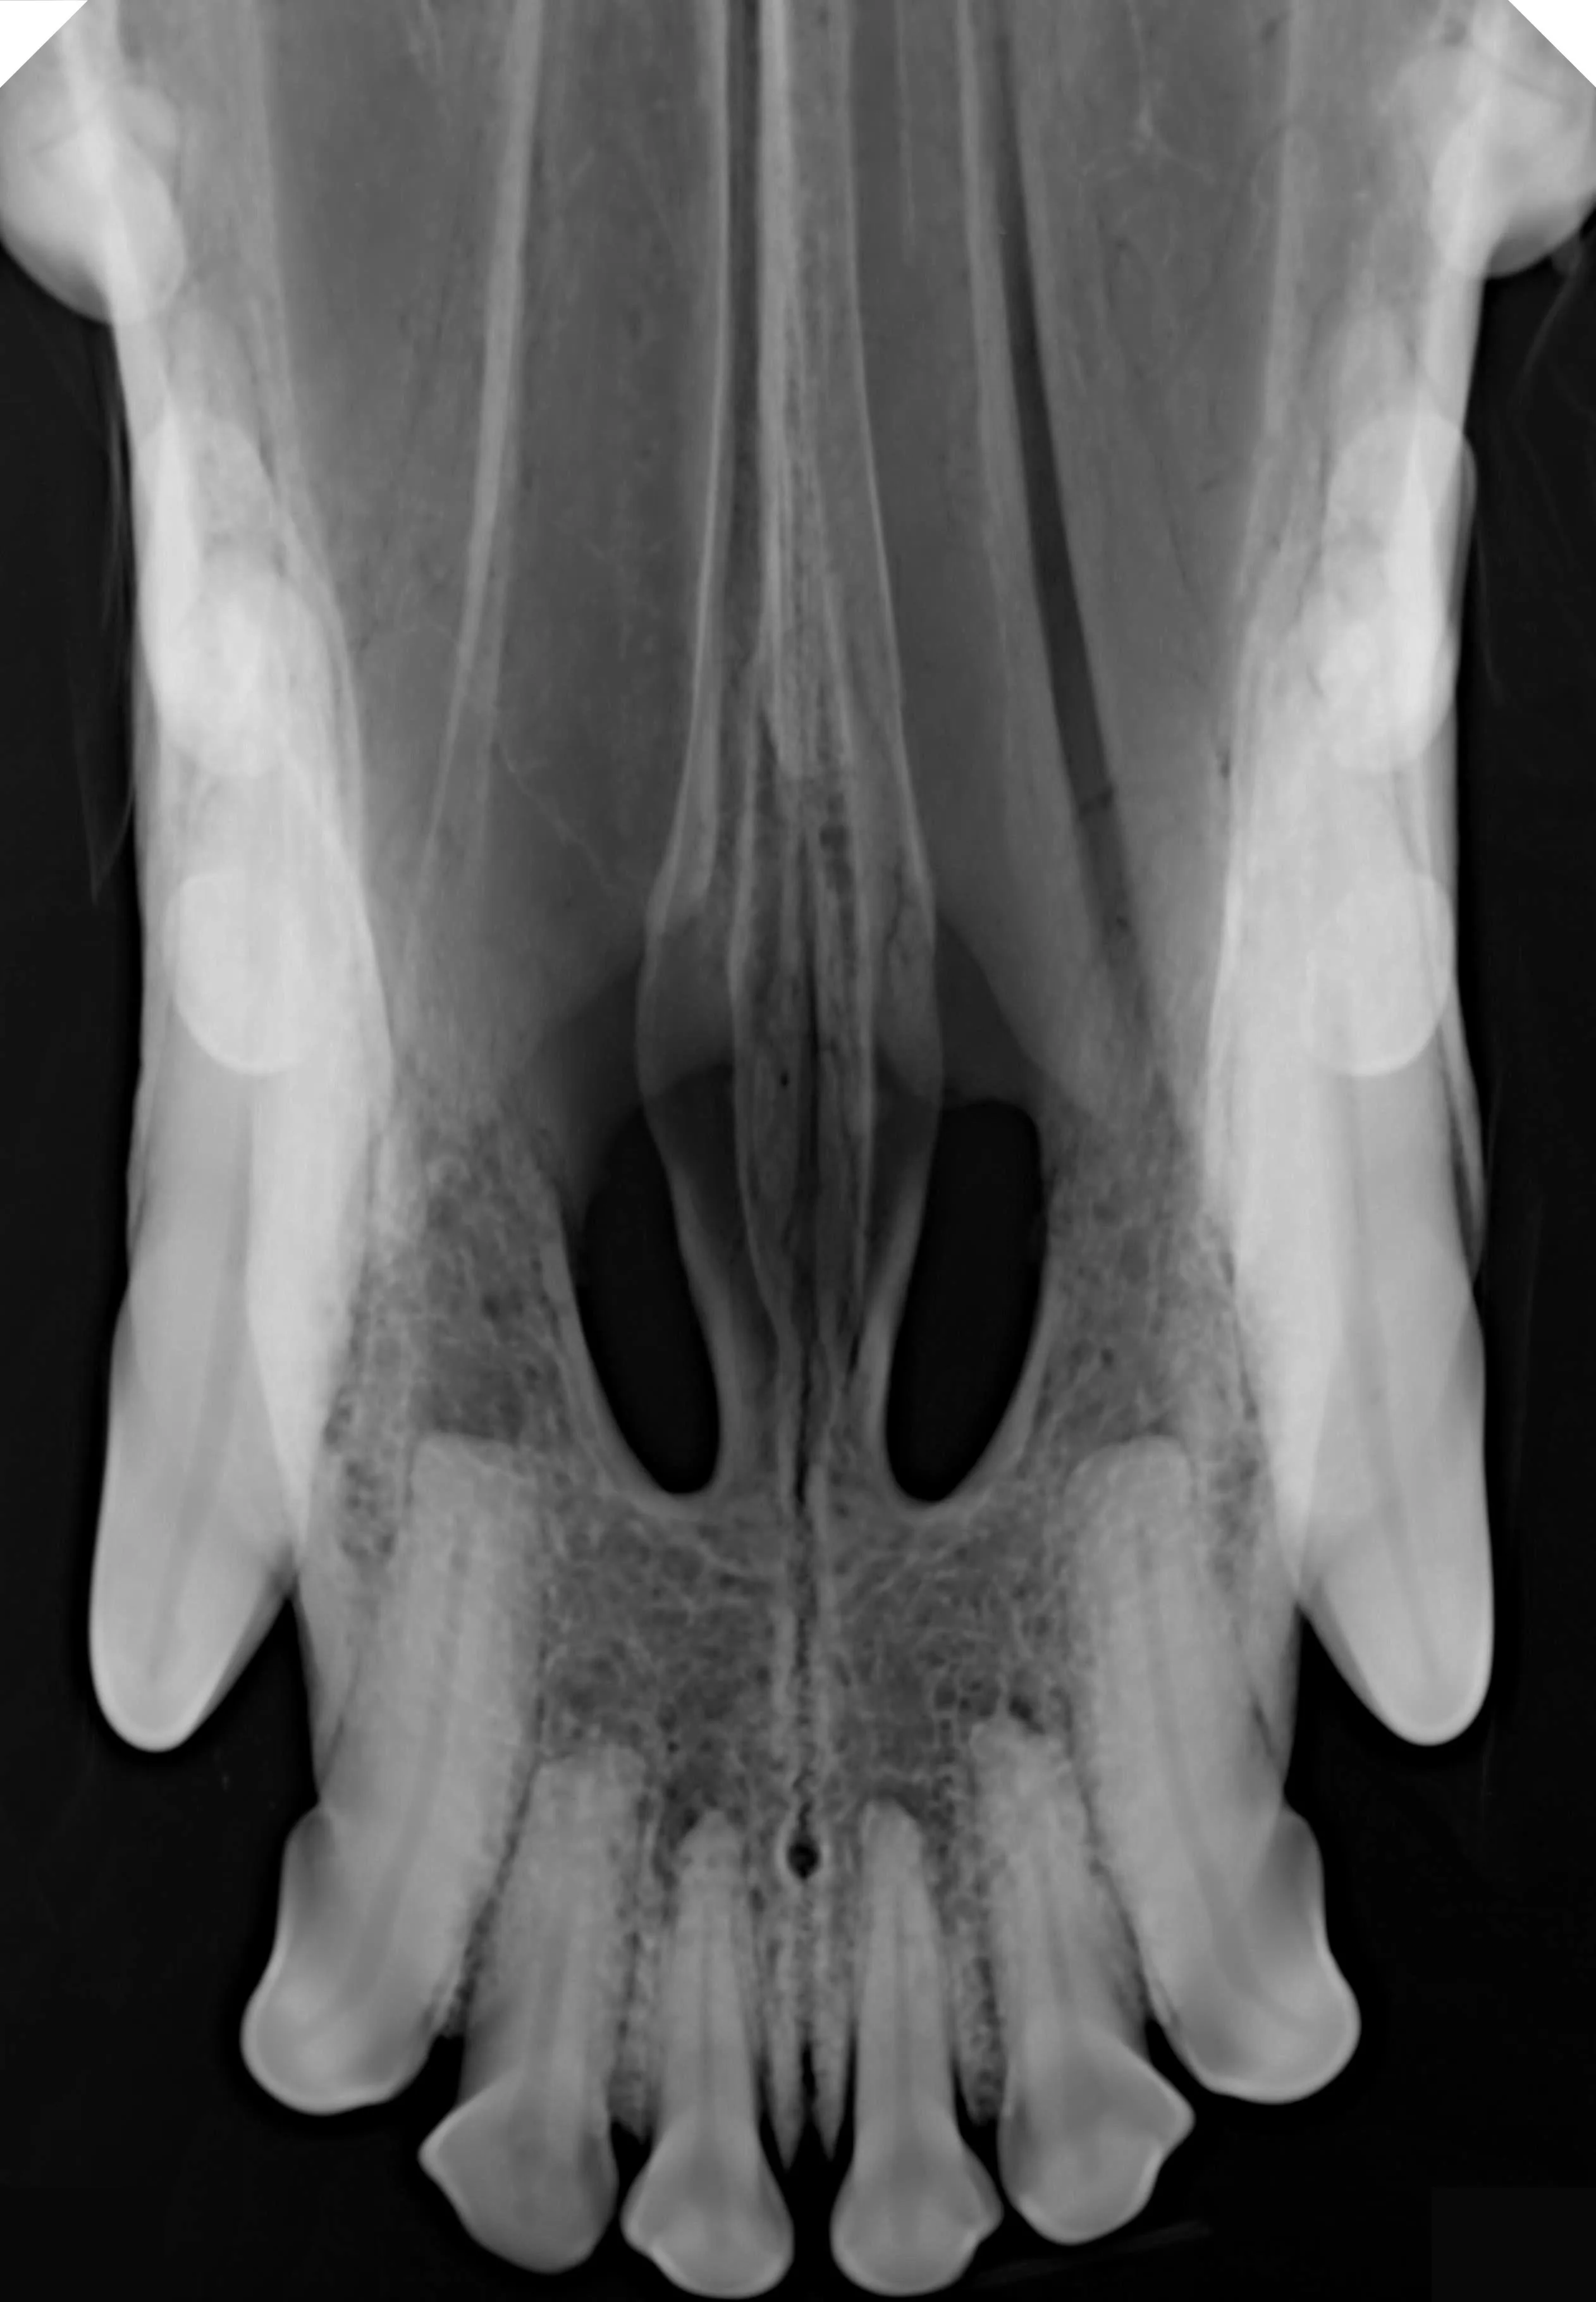

Scintillator | CsI |

Chip type | CMOS APS |

Pixel Pitch (μm) | 9.19M(2524*3640) |

Line resolution | ≥ 10lp/mm (actual value) |